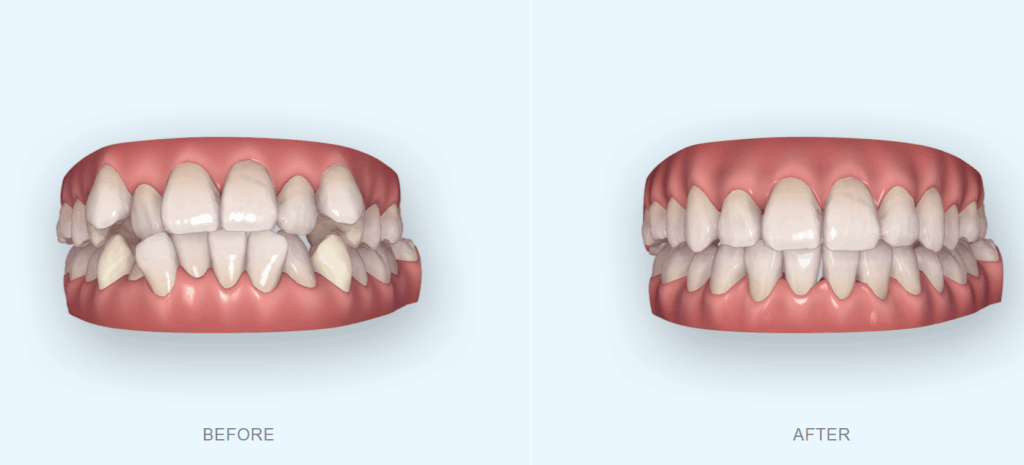

SureSmileによる治療シミュレーション

診断結果をもとに、デジタル矯正システム「SureSmile」を用いて

歯の動きを3D上でシミュレーションしました。

この工程では、

抜歯後にどのように歯が動いていくのか

八重歯がどの位置に整っていくのか

治療後の理想的な歯列ライン

などを立体的に確認しながら、精密な治療計画を立てていきます。